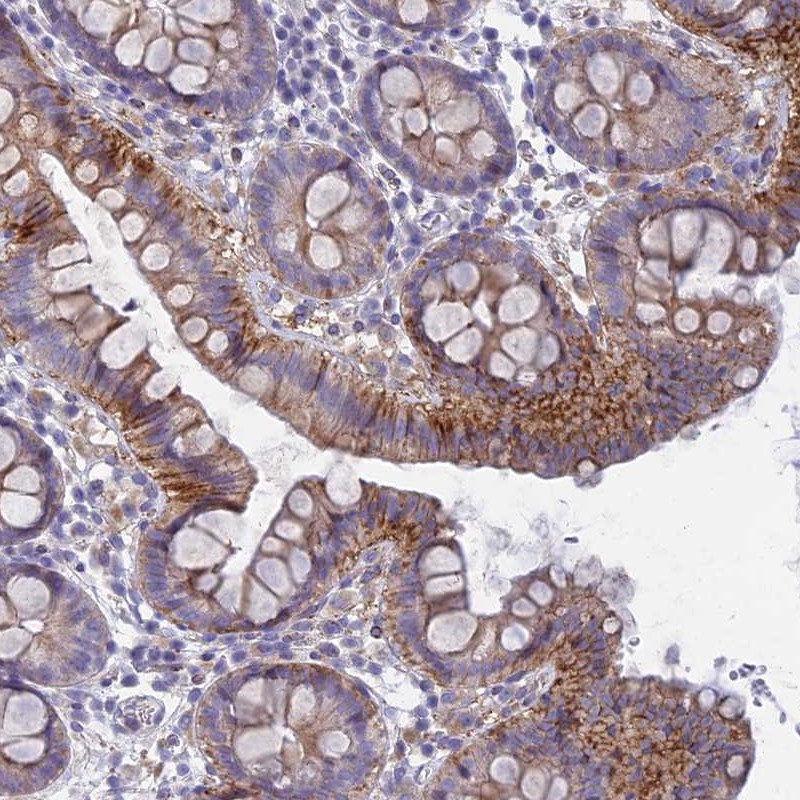

Immunohistochemical staining of human colon shows strong cytoplasmic and membranous positivity in superficial glandular cells.